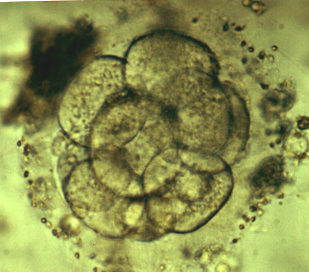

8-16 cells stage embryo

expanding blastocyst